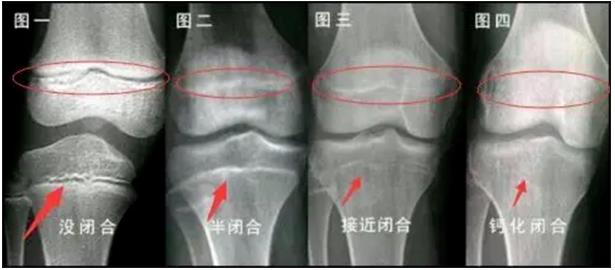

??? ???, ???, ???(塑形期) ? ???? 4?? ????? ??. ??? ??? ?? ??? ??? ??? ?? ??? ?? ????? ?????? ???. ??? ??? ???? ???? ?? ?? ???? ??? ??? ??? ? ??.

3~11?? ??? ??? ???? ???? ??? ??? ?? ??? ??? ????? ??. ???? 11~16?? ???? ????? ??? ?? ???? 12~18?? ??? ????.